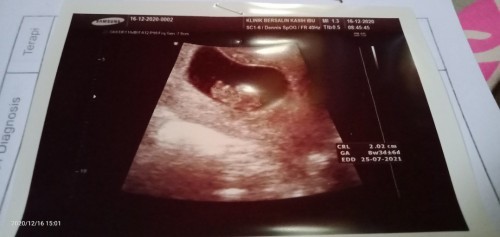

Umur kehamilan 8 minggu, ukuran 2,2 cm, detak jantungnya keras banget,, adakah yang sama bunda??????